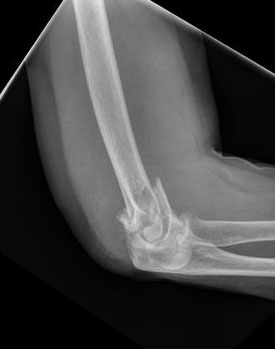

Fractura supracondílea de codo.

Fractura supracondílea de codo.Tras reducción y osteosíntesis.

Fractura supracondílea de codo. Tratamiento con agujas.